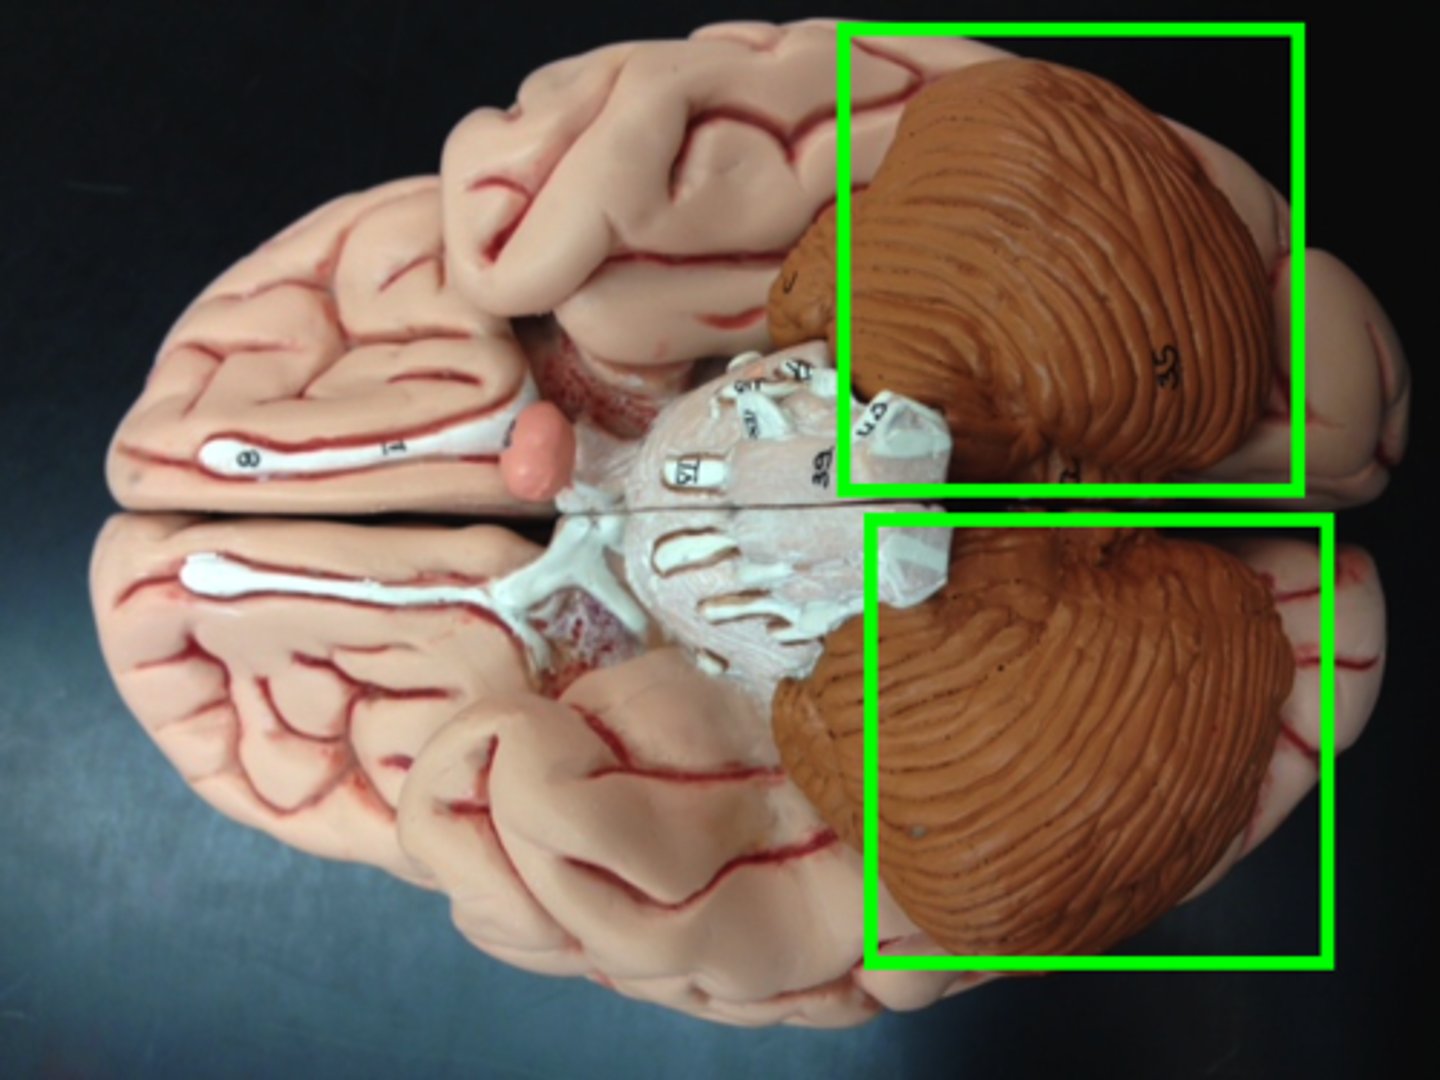

cerebellum

right and left cerebellar hemispheres

vermis

cerebellar cortex

brown

arbor vitae

white matter

tentorium cerebelli

between cerebrum and cerebellum